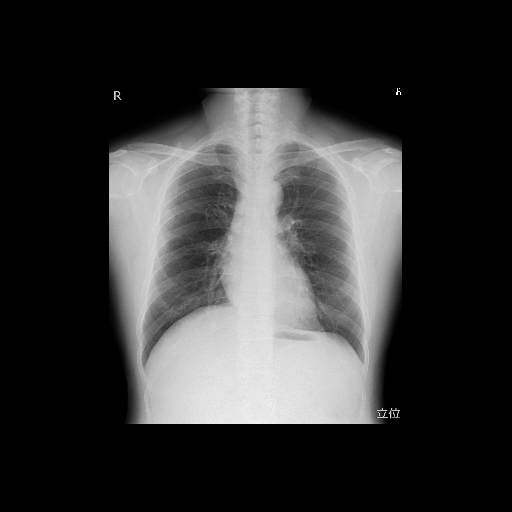

X線を照射して、体内の様子を写し出す検査です。胸部・腹部だけでなく、全身の骨を撮影することが可能です。

胸部では、肺の病変を見つけるだけでなく、大動脈や心臓の形態も検察することができます。

全身の骨の撮影では、骨折や関節の変化を明瞭に観察することができます。